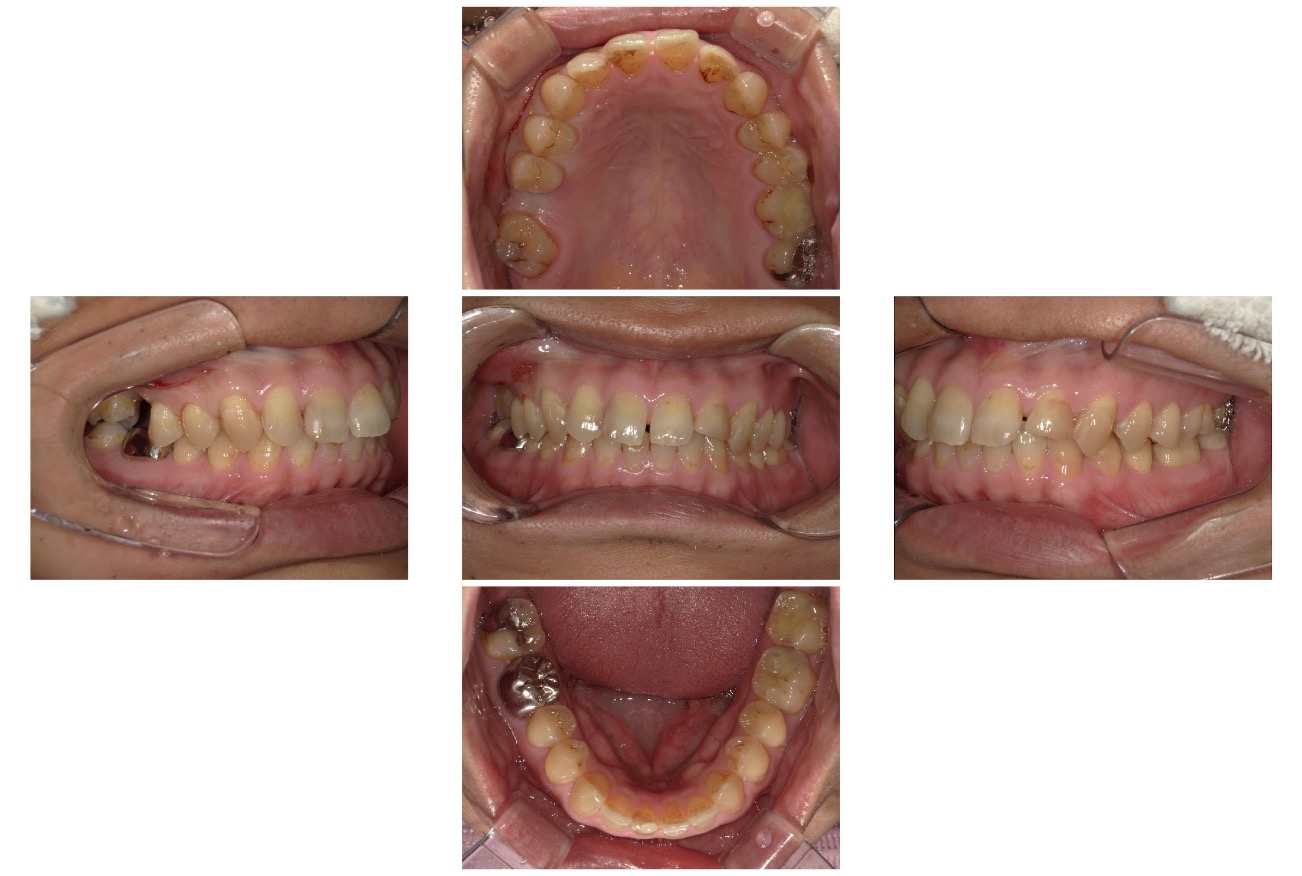

Case.04

治療前

治療後

| 主訴 | 受け口を治したい |

|---|---|

| 治療 期間 | 2年 |

| 治療費 | 880,000円 (税込968,000円) |

| 治療 内容 | インビザライン 顎間ゴム |

| 治療の リスク | 1日に20時間以上装着しないと、予定通りに歯が動かないことがあります。 装着後数日痛みがあります。 |